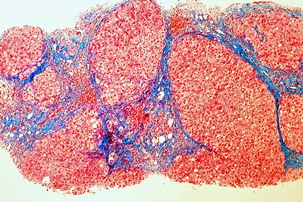

황달의 원인

황달이 생기는 이유는 담즙색소라고 알려진 빌리루빈이 과도하게 생기기 때문입니다. 빌리루빈은 우리 몸의 오래된 적혈구가 파괴되면서 생기는 물질인데요. 이 물질은 담즙에 녹아서 우리 몸의 배설물과 함께 배출이 되는 것이 정상적이지만 빌리루빈의 과잉생산이나, 간의 장애, 간세포나 담도의 손상에 의해 빌리루빈이 역류할 경우 발생된다고 합니다.

3. 자몽

자몽에는 간을 보호하는 물질이 함유되어 있습니다. 이는 항산화물질로 간 섬유증 발병을 감소시킨다고 보고 있습니다. 자몽은 염증과 싸우면서 간 건강을 유지하는데 좋은 과일입니다.